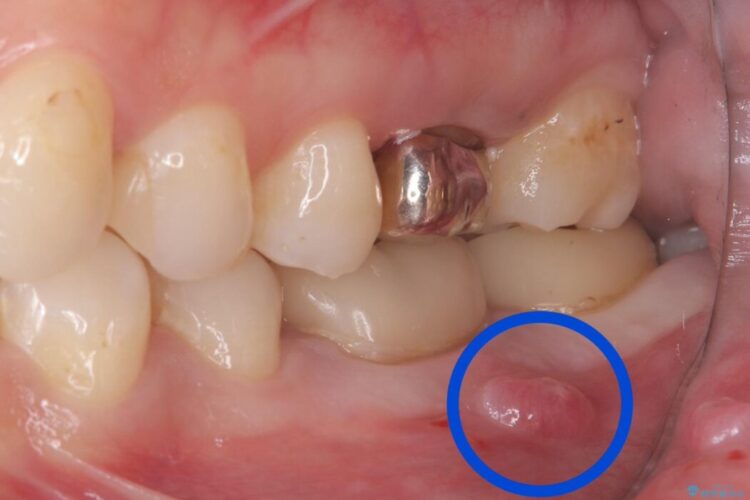

左下6番の周りに大きく透過像(影)を認め、再根管治療後の予後が良くない可能性が高く、当院でも抜歯が適応となる状態だと判断しました。

欠損部に対しインプラント治療や歯牙移植(左下の親知らずの移植)、ブリッジを提案し、歯牙移植を行うこととなりました。